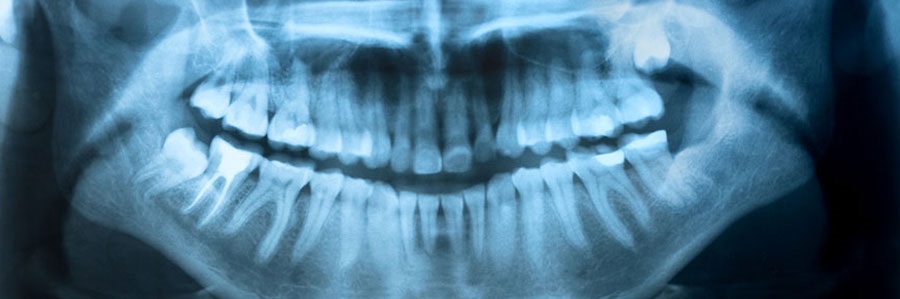

بسیاری از بیماریهای دندانها و بافتهای احاطه کننده آنها هنگام معاینه معمول دندانپزشکی دیده نمی شوند. از جمله مواردی که یک معاینه رادیوگرافیک آنها را آشکار می کند عبارتند از: نواحی کوچک پوسیدگی بین دندانها، عفونت استخوان آبسه یا کیست، آبنورمالیتی های تکاملی، بعضی انواع تومورها. کشف و درمان زود هنگام مشکلات دندانی از هدر رفتن پول و زمان جلوگیری کرده و باعث ممانعت از بروز ناراحتی های غیر ضروری می گردد. معاینه رادیوگرافیک، مشکلاتی از ساختار دهان را که در طی معاینه معمولی دیده نمی شود، آشکار می سازد. اگر شما تومور پنهانی داشته باشید، رادیوگرافی ها ممکن است به شما کمک کند که زودتر آن را کشف و درمان کنید.

نحوه عمل اشعه X